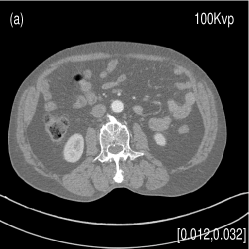

We also evaluated the proposed PWLS-TNV- method using clinical pelvis data. The patient’s pelvis data was acquired by Siemens SOMATOM Definition flash CT scanner using DECT imaging protocol. Table 4 lists acquisition parameters in the pelvis data scan. Fig. 5 shows the high- and low-energy CT images of the pelvis data. Fig.5 (b) shows selected basis materials, bone, iodine, muscle, fat and air, and their assosicated ROIs highlightened in white dashed line circles. We implemented the Direct Inversion method in mendonca2014a and used its results as the initialization for the PWLS-EP-LOOP xue2017statistical and the proposed PWLS-TNV- method. Fig. 6 shows the decomposed material images by the Direct Inversion, the PWLS-EP-LOOP and the PWLS-TNV- method. Table 5 summarizes the means and noise STDs of the decomposed material images by the above three methods. The volume fraction (VF) accuracies are , , and for the Direct Inversion method, the PWLS-EP-LOOP method and the proposed PWLS-TNV-, respectively. Compared with the Direct Inversion and PWLS-EP-LOOP method, the proposed method improves the VF accuracy by and respectively. The proposed PWLS-TNV- method decomposes basis material images more accurately, suppresses noise and decreases crosstalk, while retaining spatial resolution of the decomposed images compared to the other two methods.